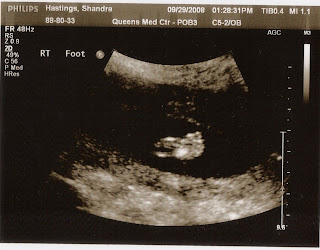

Yes!  It's a boy!  If word on the street hasn't reached your neighborhood yet, we are pregnant.  I am about 18 weeks now and feel so blessed with my easy pregnancy (so far).  Today we were able to hang out with the baby for almost an hour during the ultrasound.  We got to see him moving, cross his legs and uncross them, open and close his mouth, and cover his face with his cute hands.  He was very active today, but also squeezed in a little power nap during the ultrasound.  Here are a few of our favorite photos.

He has 5 toes!

It's a boy!